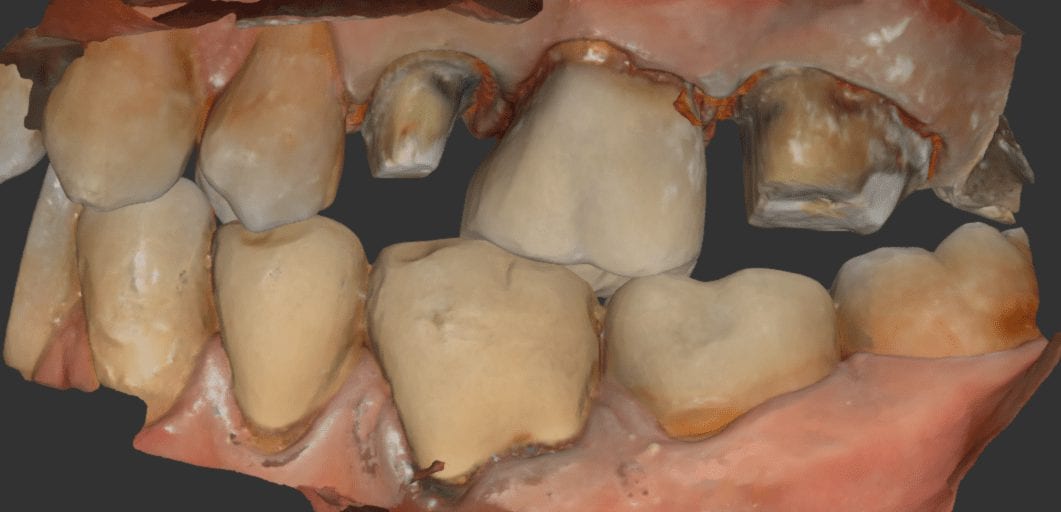

CASE SET UP FOR PREMOLAR SCAN IN MEDIT

CASE SET UP FOR MOLAR IN MEDIT